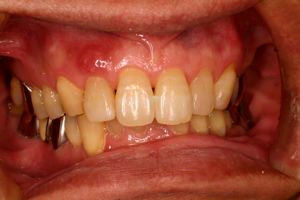

術前口腔内(正面観)